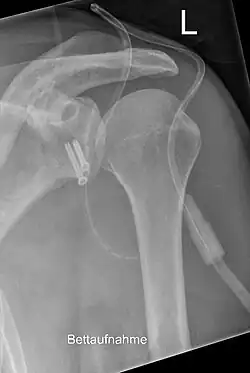

Eine Glenoidfraktur, die die gesamte Schulterpfanne betrifft, entsteht dagegen meist durch einen Unfallmechanismus mit einer sehr hohen Aufprallenergie, etwa bei einem Verkehrsunfall.[5] Begleitverletzungen des Schlüsselbeins, des Brustkorbes, des Armplexus und der Halswirbelsäule sind nicht selten. Zur genauen Diagnostik ist meist eine Computertomographie unerlässlich. Bei einer Verschiebung der Fragmente von 3 mm oder mehr ist eine operative Reposition und Osteosynthese indiziert, um eine vorzeitige Arthrose durch die nicht korrigierte intraartikuläre Stufenbildung zu vermeiden. Die Fixierung erfolgt in der Regel mit Fäden, Drähten, Schrauben oder Platten, die entweder mittels einer arthroskopischen oder einer offenen Operation eingebracht werden.